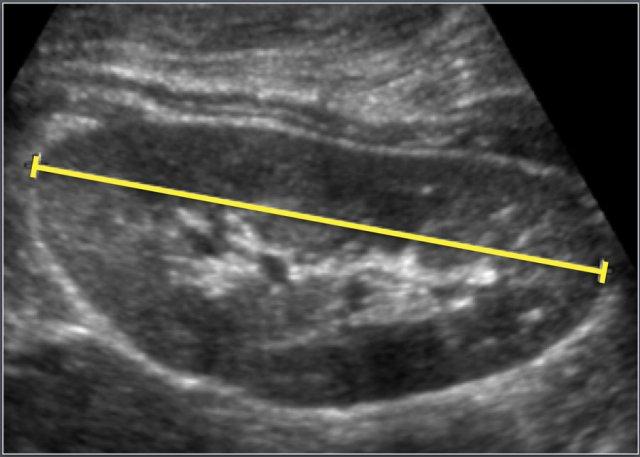

Đo chiều dài thận trên siêu âm.